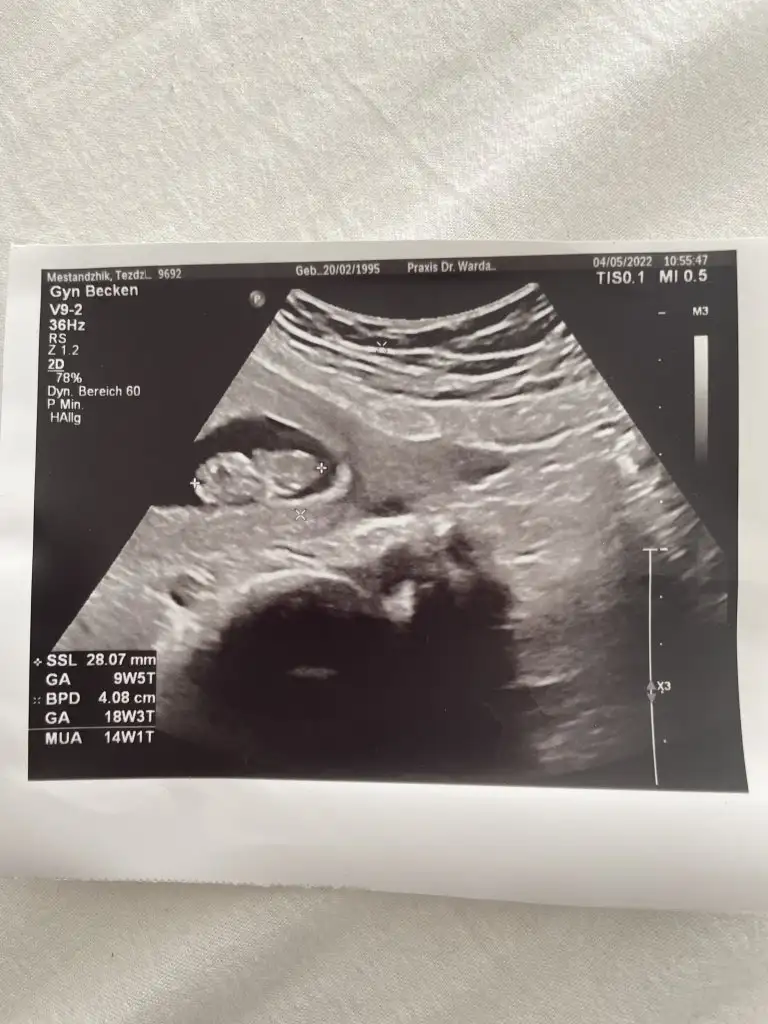

9+5 karından bakıldı banada tahminde bulunur musunuzSelam Kızlarbir çok kişi gruplardan beni bilir. Yine yetiştim imdatlara

9+5 karından bakıldı banada tahminde bulunur musunuz